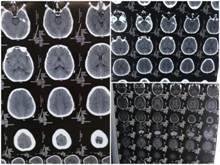

▲术前CT片

由于该患者肿瘤位置较深,肿瘤位于运动、语言区,周围重要血管和神经密集,属于高风险高难度手术。经过神经外科团队慎密的术前讨论,决定为患者在神经导航显微镜下行左顶枕肿瘤切除术。

术后患者恢复良好,患者复查头颅CT显示,术区无出血,肿瘤完全切除,手术效果好。